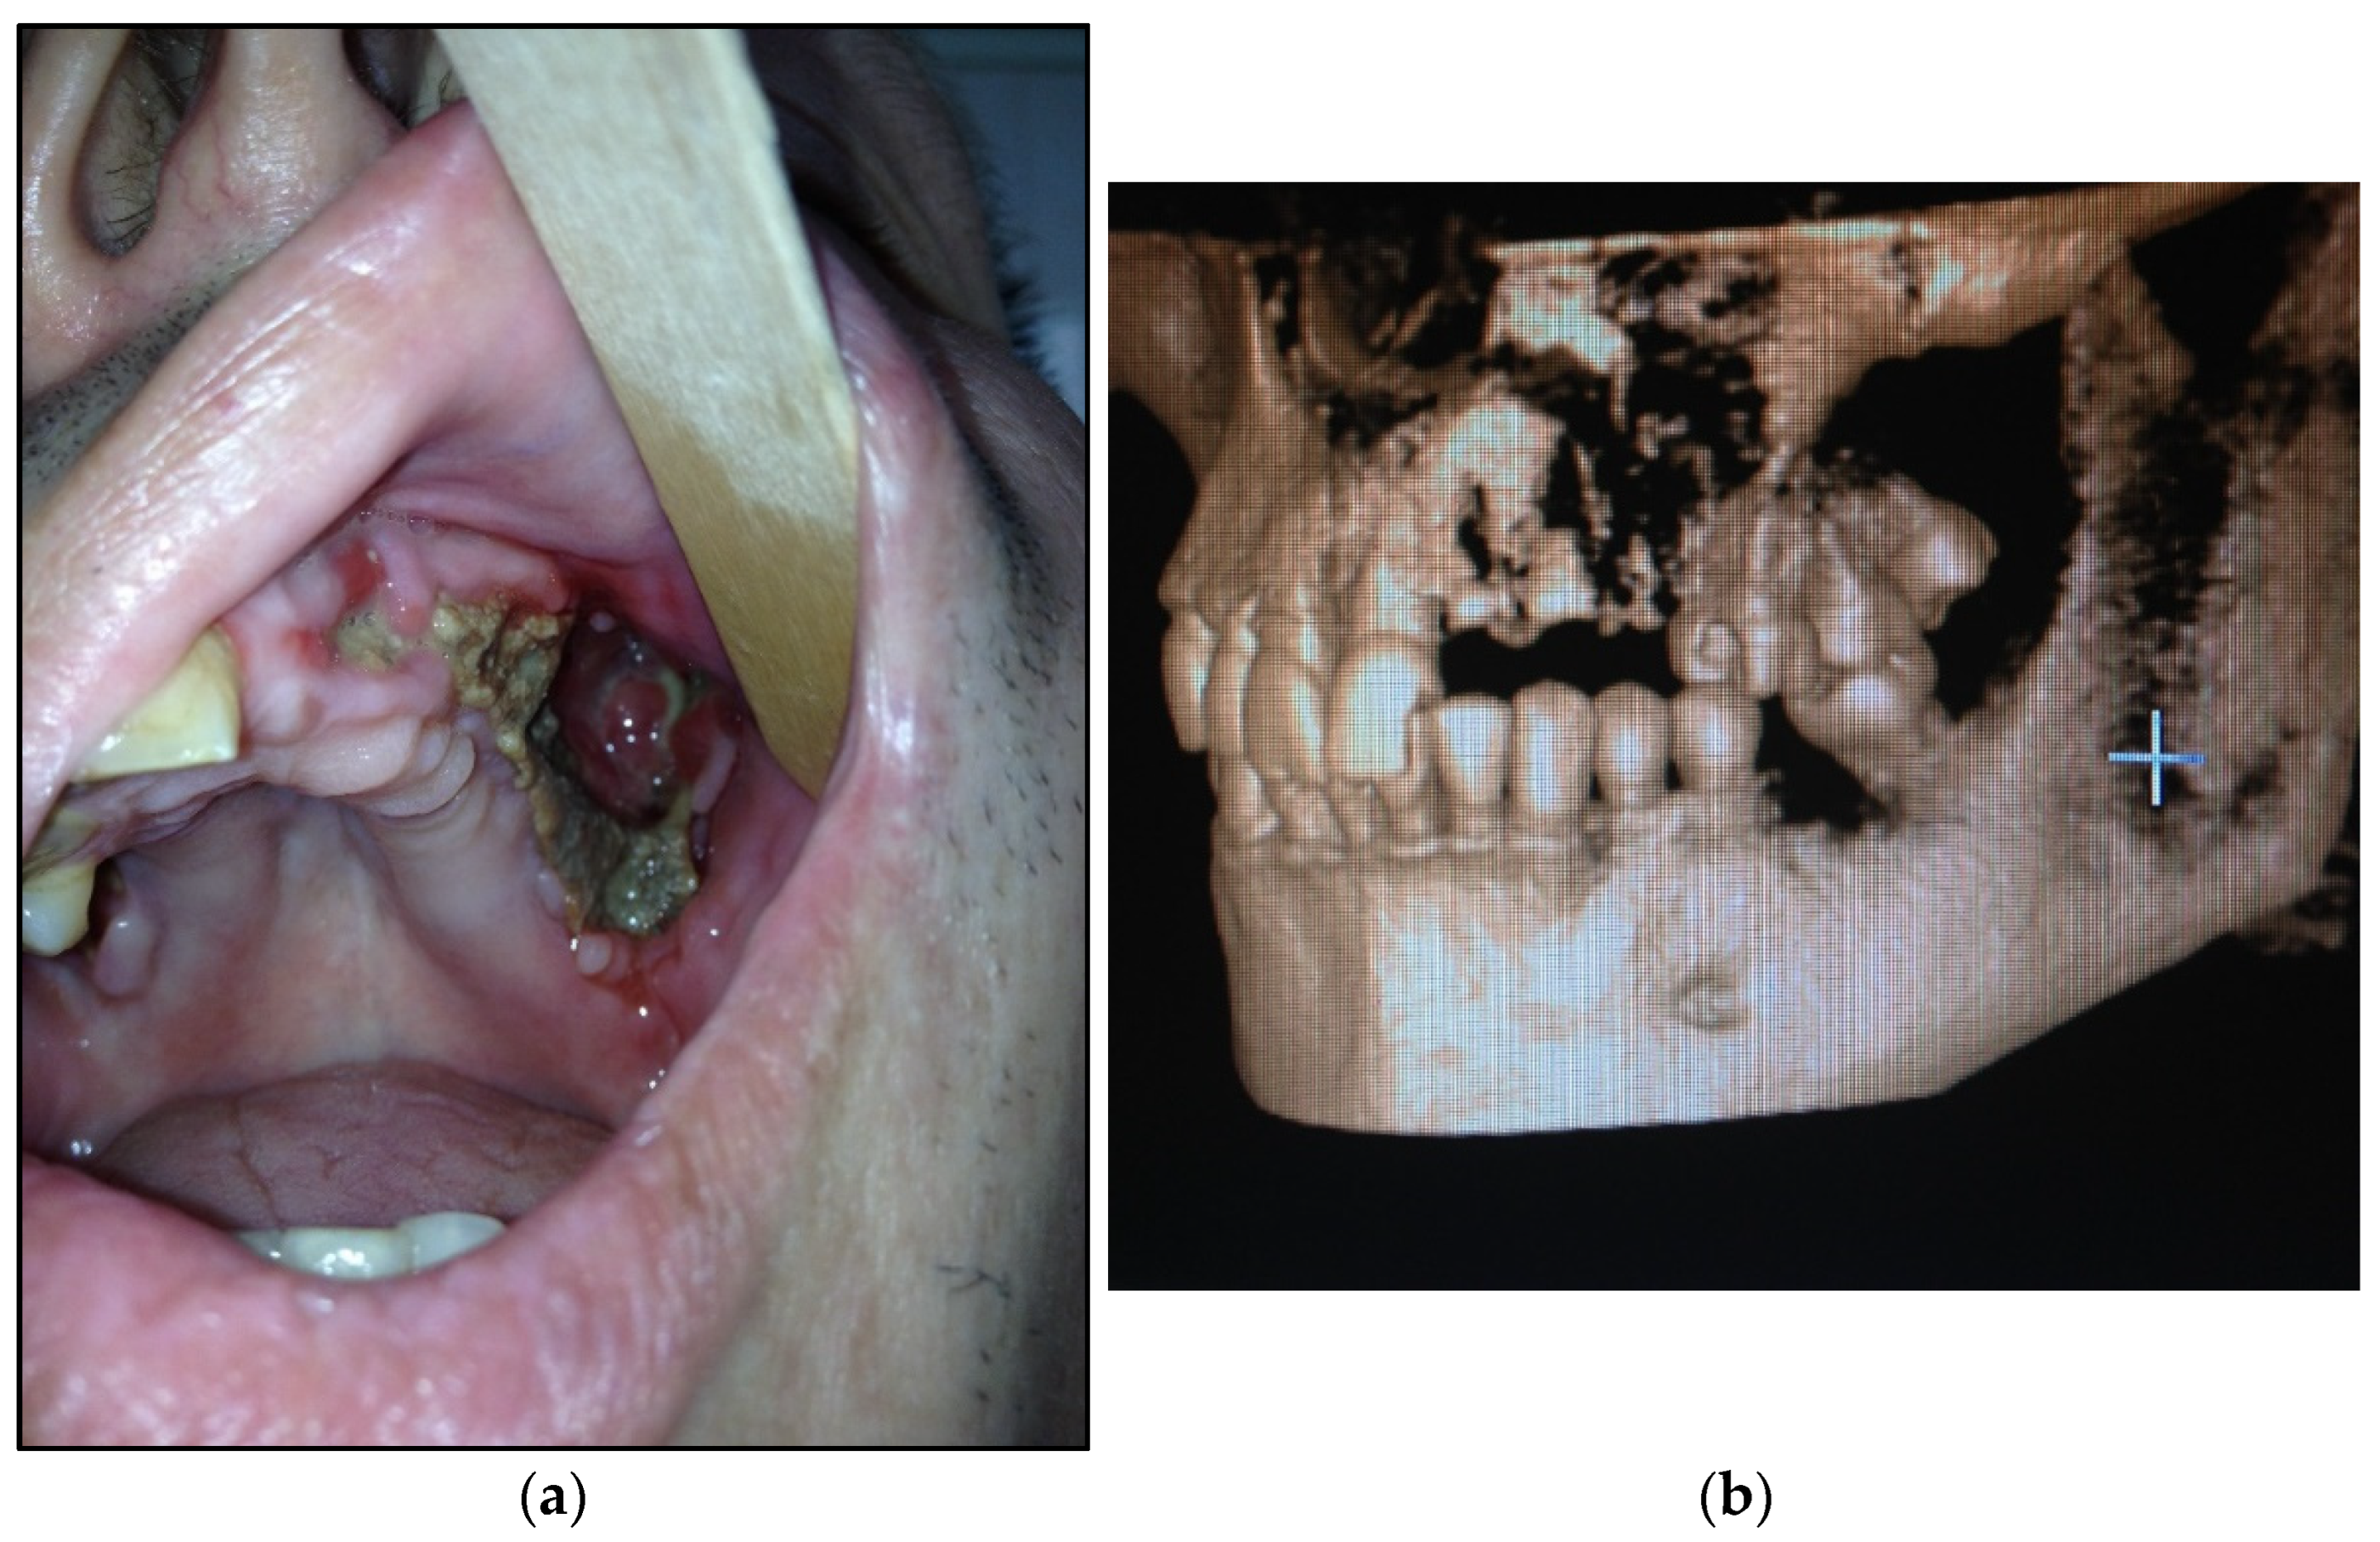

- Type 1: patients with local pathological process in maxilla (1 or 2 teeth/dental sockets are included)—15 patients (30%) (Figure 1a,b);

- Type 2: patients with maxilla involved (at least three teeth are included)—14 patients (28%) (Figure 2a,b);Figure 2. (a) Patient with type 2 toxic phosphorus osteonecrosis. Intraoral view; (b) patient OPG.